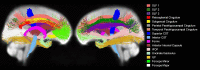

Aging is associated with widespread alterations in cerebral white matter (WM). Most prior studies of age differences in WM have used diffusion tensor imaging (DTI), but typical DTI metrics (e.g., fractional anisotropy; FA) can reflect multiple neurobiological features, making interpretation challenging. Here, we used fixel-based analysis (FBA) to investigate age-related WM differences observed using DTI in a sample of 45 older and 25 younger healthy adults. Age-related FA differences were widespread but were strongly associated with differences in multi-fiber complexity (CX), suggesting that they reflected differences in crossing fibers in addition to structural differences in individual fiber segments. FBA also revealed a frontolimbic locus of age-related effects and provided insights into distinct microstructural changes underlying them. Specifically, age differences in fiber density were prominent in fornix, bilateral anterior internal capsule, forceps minor, body of the corpus callosum, and corticospinal tract, while age differences in fiber cross section were largest in cingulum bundle and forceps minor. These results provide novel insights into specific structural differences underlying major WM differences associated with aging.